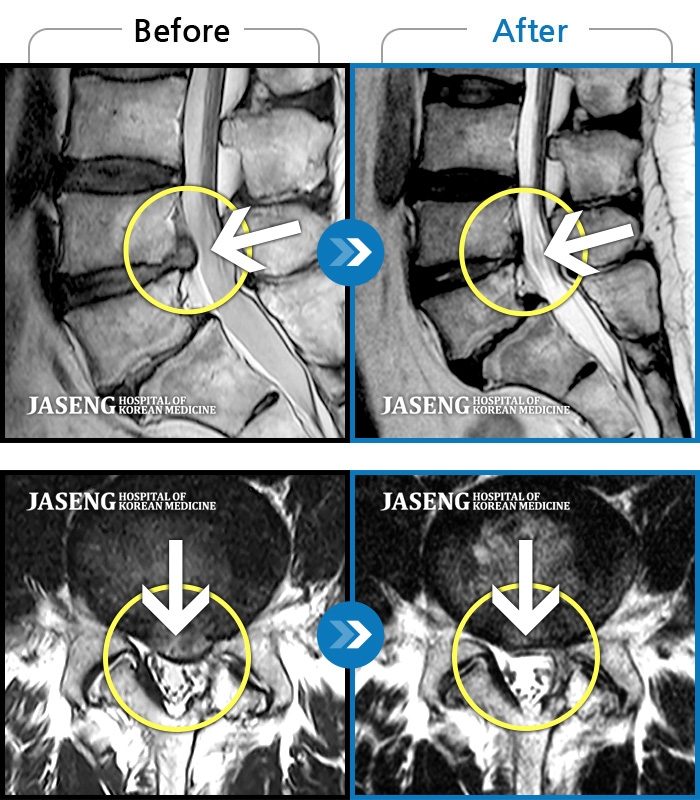

- 허리디스크

서울의 모 대학 병원에서 디스크 수술의 받으시고 1년 만에 다시 마비가 와서 불안한 마음으로 재수술

을 준비 하던 중에 세미급 병원 이사님으로 계시는 지인 분께서 강남 자생의 이진호 원장님을 추천 주셔서 수술 전에 반신반의 하는 마음으로 찾아 뵈었습니다.

왜 진작에 이진호 원장님을 찾아 뵙지 않았는지...정말 후회 합니다. 외과적 수술 전에 찾아 뵈었으면 나이 드신 어머니가 고생하지 않으시고 편안한 환경, 나이스한 성격에 유능하시고 환자의 치료에 진심이신 원장님의 치료를 받으며 완쾌하셨을 터인데... 아들로써 그동안 어머님께 무관심했던 것 아닌가 이진호 원장님의 치료를 받으며 하루 하루가 다르게 상태가 호전되어가는 어머님의 허리를 보며 마음이 무거웠습니다. 이진호 원장님께 무한한 감사를 드리며 글을 올립니다. 최고의 명의 이진호 원장님 정말 감사드립니다. -

추나요법등 허리디스크 질환에 대한 원인과 결과에대한 치료와 전반적인 상세한 설명에 진심으로 감사드립니다.

여러 정형외과,통증의하꽈,한의원에 치료하러 다녔지만 이진호원장님께서 영상으로 설명해주신것 같이 상세한 설명을 처음 듣습니다.